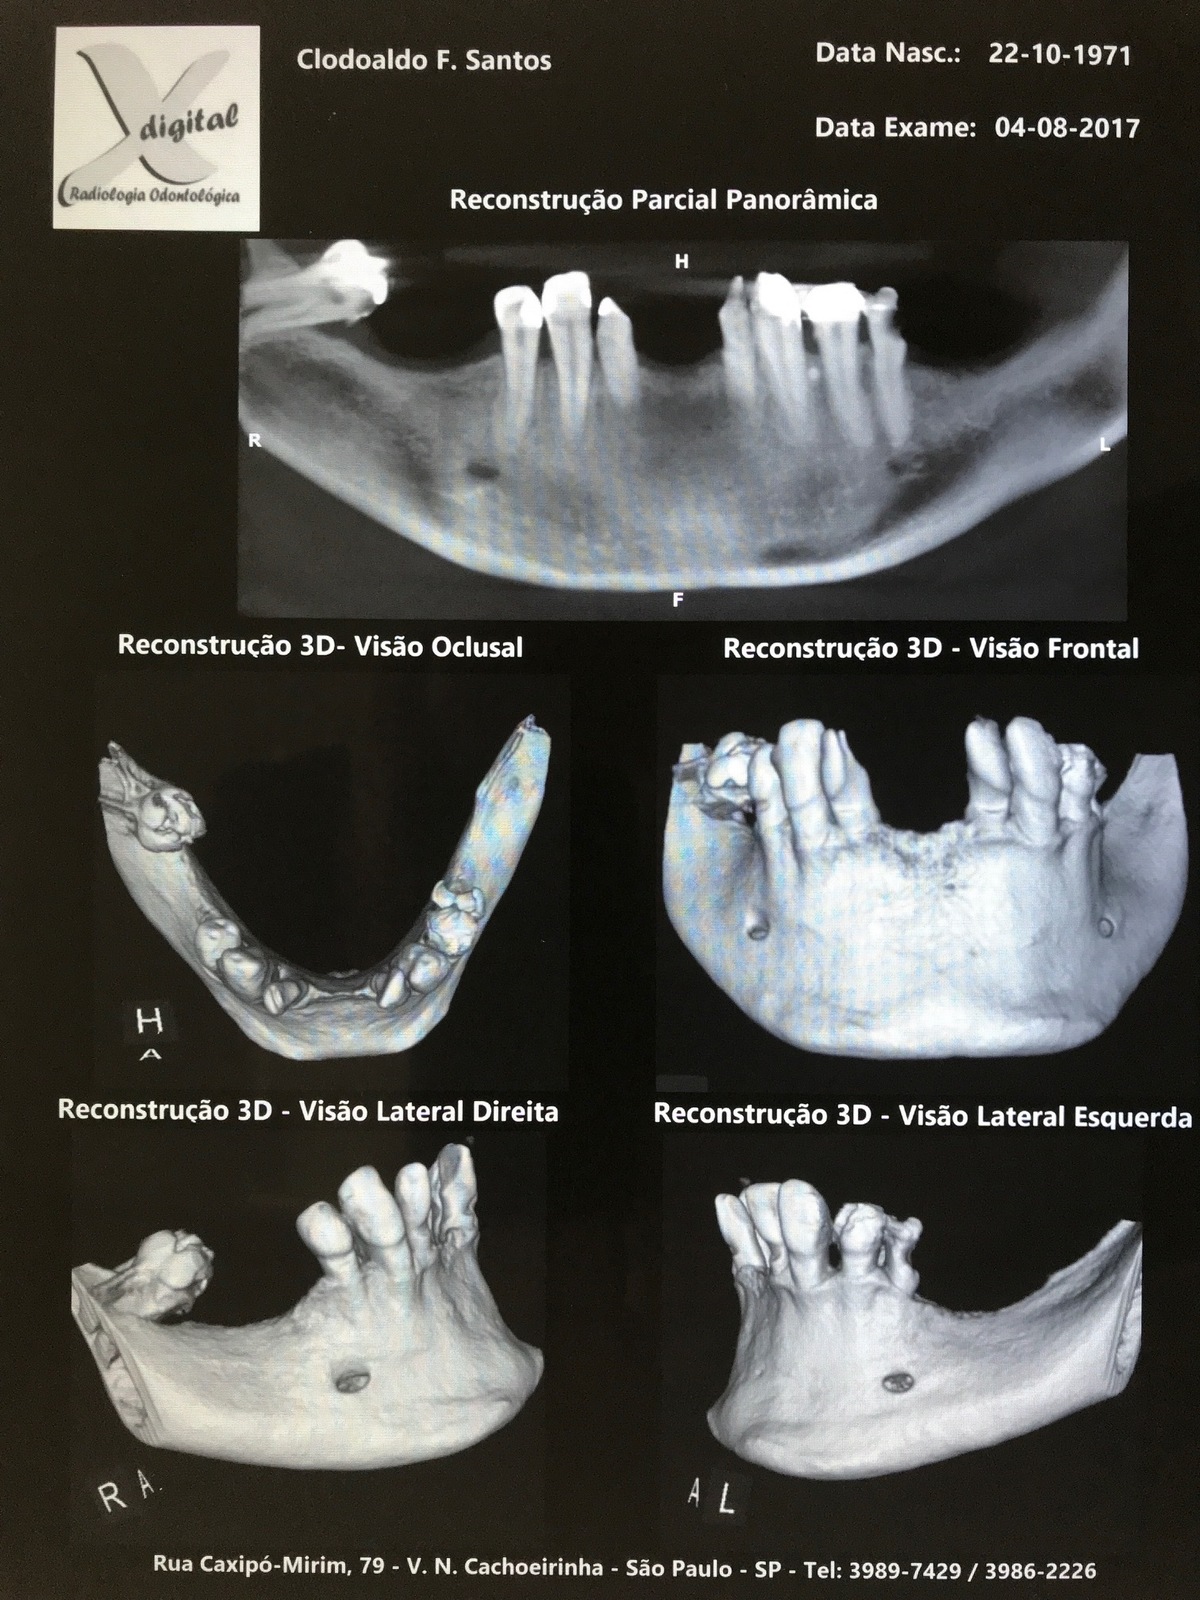

PRÓTESE TOTAL FIXA EM IMPLANTES

C.F.S.